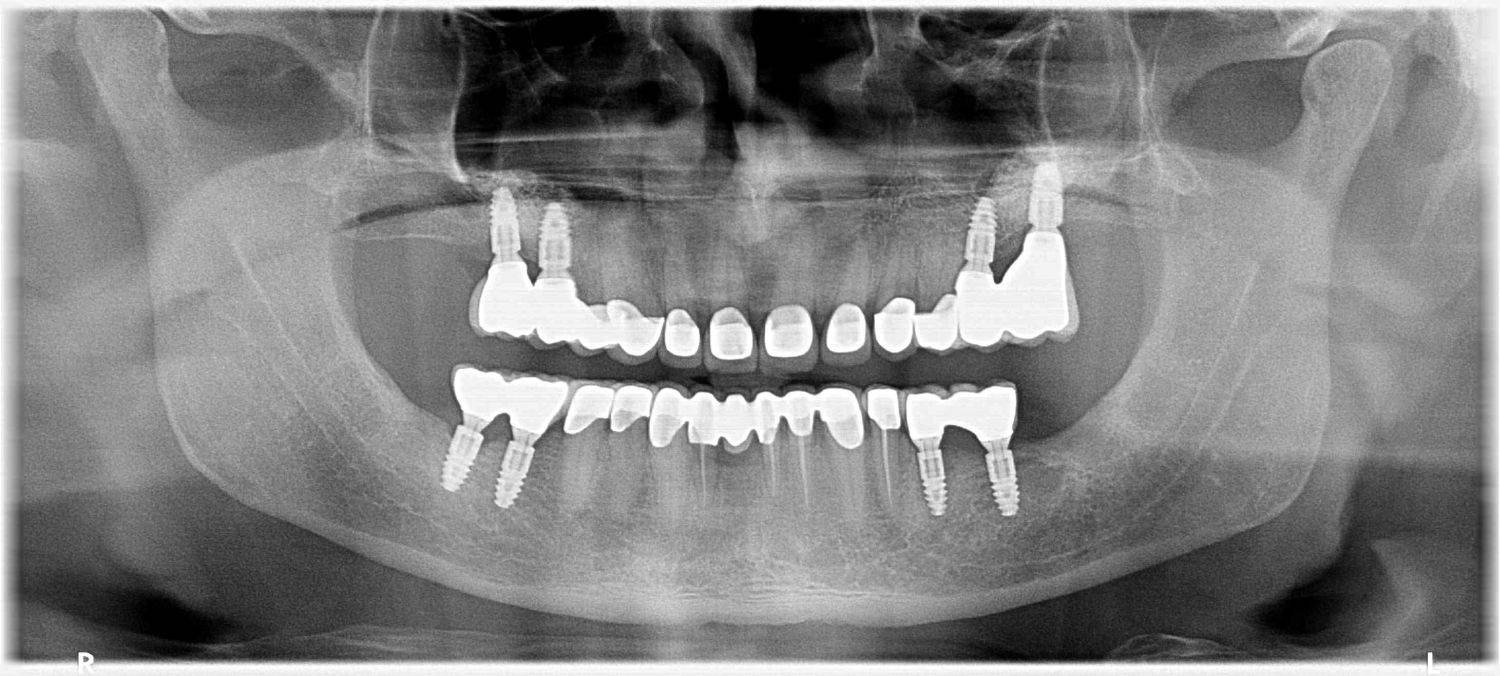

A páciens fogágybetegség miatt érkezett hozzánk. A felső fogak menthetetlen állapotban voltak. All on 6 megoldásként a felső fogak eltávolításakor 6 implantátum került beültetésre és a páciens azonnal egy fix ideiglenes hidat kapott. 4 hónapos gyógyulási idő után készült el a felső fémkerámia leplezésű körhíd.